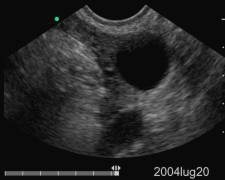

Data inserimento: 09 /11/2004Data esame: 13/08/2002 Strumento: Sonosite Età paziente: F 28 anni Gravidanza iniziale, III settimana di gestazione. Elaborazione digitale: Andrea Dini

Piccola camera gestazionale

Corpo luteo